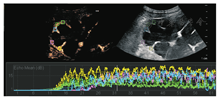

使用QLAB定量分析软件对DICOM医学影像格式数据进行分析。选取注药内1 min图像,双侧肾脏各5个固定取样框的面积为25 mm2的正方形选择框置于与声束垂直、保持同一深度、位置的外层肾皮质内,如图1。对感兴趣区域进行动态分析研究,获得肾实质灌注的时间-强度曲线TIC,并得到相关定量参数包括上升支斜率A、曲线下面积AUC、曲线峰值强度PI、达峰时间TTP。反复核对收集的资料及数据。最终由专人再次核对、确认数据,录入数据库。

注:不同色块代表不同感兴趣区

选取两组肾脏各5个感兴趣区域,每个ROI区域为正方形5 mm×5 mm选择框,选取注药后1 min图像,对其进行动态分析研究,应用QLAB软件,绘制肾皮质TIC曲线。对照组TIC曲线上升陡直,迅速达到峰值强度,而后缓慢下降至基础水平,见图2。实验组TIC曲线上升平缓,达到峰值强度延迟,下降缓慢,且峰值强度较低,造影剂消退较对照组快,见图3。

应用QLAB软件定量分析实验组及对照组TIC曲线,见图4,获得五组相关定量参数包括A、AUC、PI、TTP,分别取其均数。实验组及对照组的CEUS定量参数用两配对样本t检验比较,见表1。